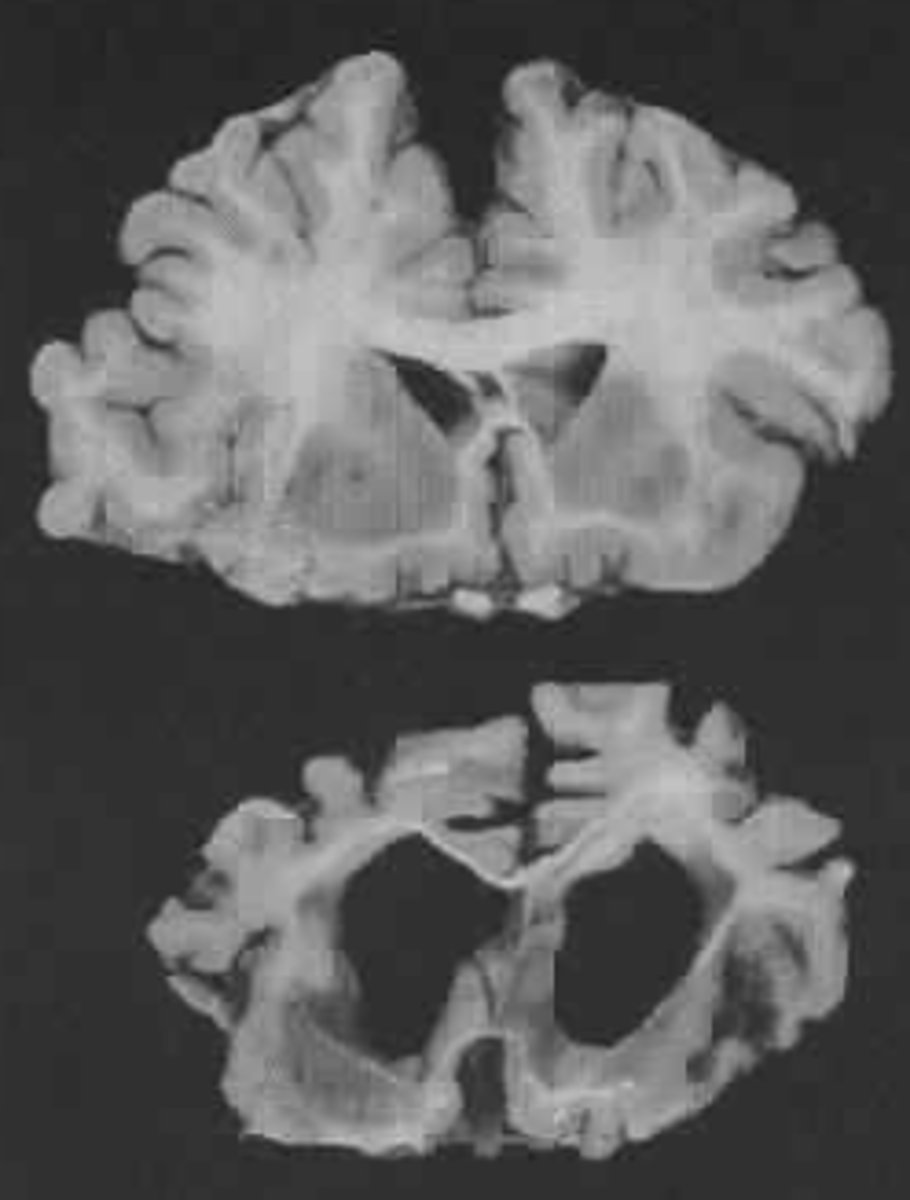

Dementia

An umbrella term for a collection of symptoms that fit the description of multiple conditions that result in changes to the brain

What structural changes in the brain are occurring with dementia?

Cells are shrinking and dying

4 Truths of Dementia

1. At least two parts of the brain are dying